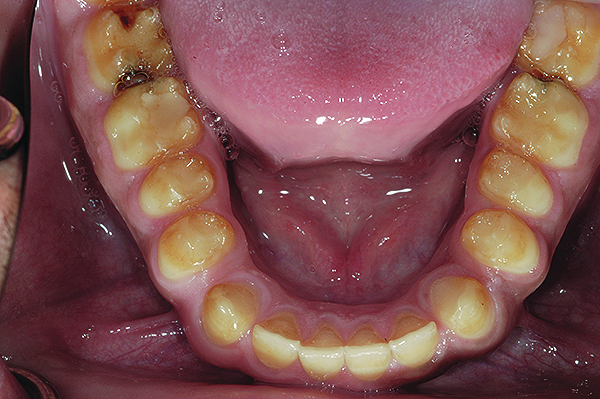

A thorough clinical examination and analysis were carried out to assess the esthetic and functional problems of the patient (Figure 2 through Figure 7). The medical history was non-contributory, except for mild leukoderma. Temporomandibular joint (TMJ) function was within normal range.

Figure 6. Preoperative maxillary occlusal view.

Figure 6

Figure 7. Preoperative mandibular occlusal view.

Figure 7